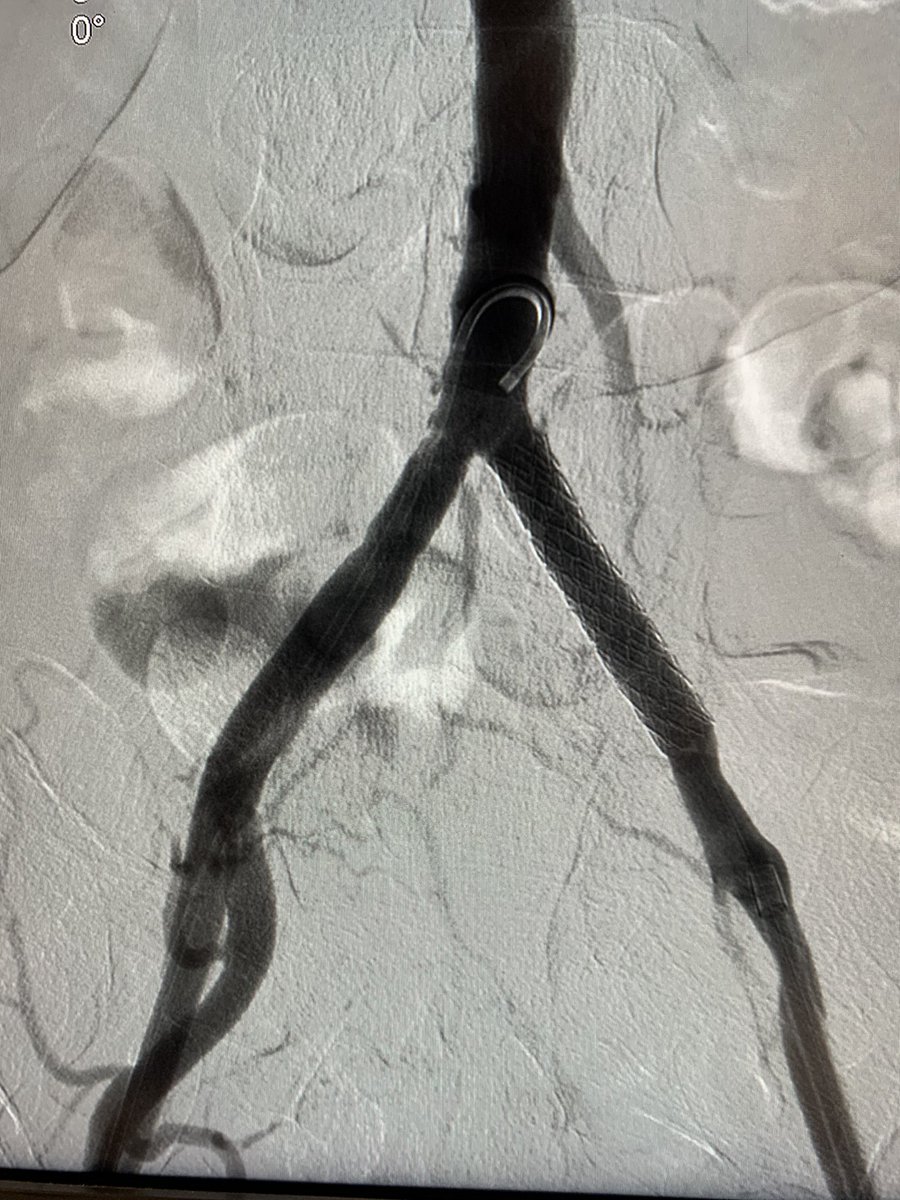

.@LucasRCmd, MPH; @HiroSparks, MD; Kara E. Masterson, MSN, NP; Scott J. Genshaft, MD; @AdamPlotnik, MD; and Siddharth A. Padia, MD, contributed to this open access article. See what they've been working on! brnw.ch/21wPx6v